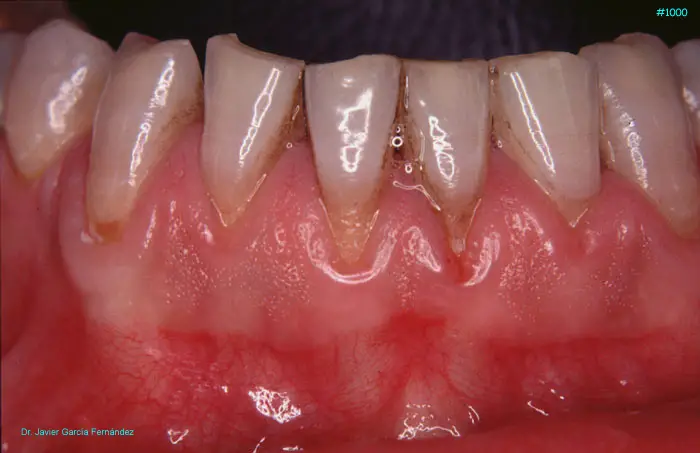

Atlas of Surgical Techniques in Periodontics. Chapter III. Atlas de Técnicas Quirúrgicas en Periodoncia